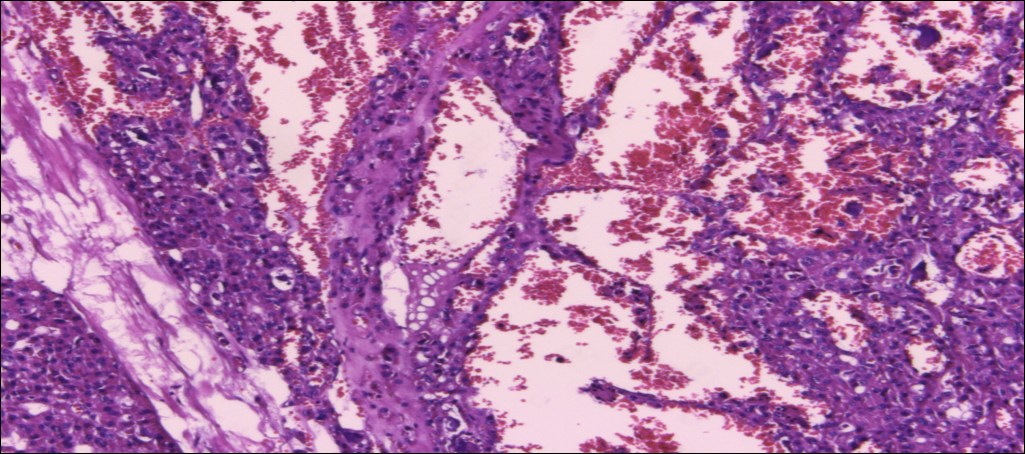

甲状腺嗜酸性细胞腺瘤

(甲状腺右叶及峡部):暗褐结节,直径6cm,包膜完整

肿物包膜完整,镜下未见明确包膜、脉管侵犯

镜下可见包膜,脉管侵犯!